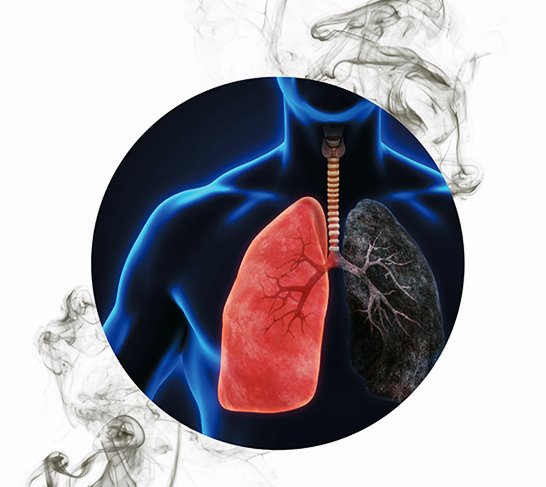

폐암 예방법

흡연은 폐암의 가장 큰 원인 중 하나입니다. 담배를 피우지 않거나 금연하는 것이 폐암 예방에 가장 효과적입니다. 만약 흡연 중이라면 의사나 금연 전문가의 도움을 받아 금연 계획을 수립하는 것이 좋습니다.